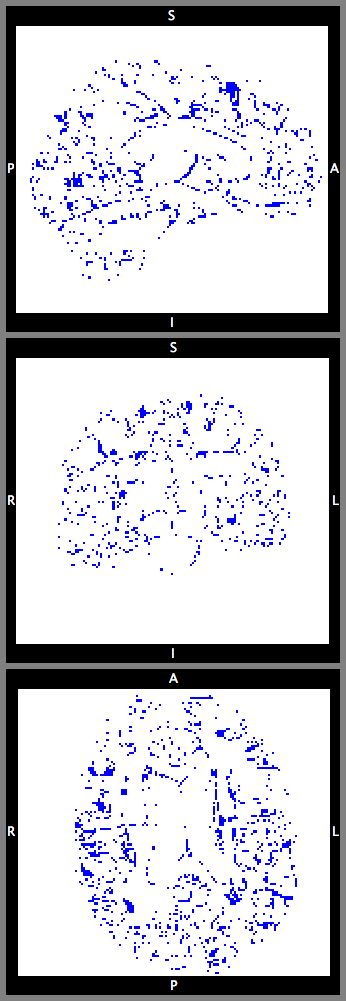

This section investigates the number of Monte Carlo samples and the segmentation performance of the proposed network. Fig. 8(a) suggests that using samples is enough to achieve good segmentation. Further increasing the number of samples has relatively small effects on the DCS. Fig. 8(b) plots the voxel-wise segmentation accuracy computed using only the voxels with an uncertainty less than a threshold. The voxel-wise accuracy is high when the threshold is small. This indicates that the uncertainty estimation reflects the confidence of the network. Fig. 9 shows an uncertainty map generated by the proposed network. The uncertainties near the boundaries of different structures are relatively higher than the other regions.

With this theoretical insight, we are able to estimate the uncertainty of the segmentation map at the voxel level. We extend the segmentation network with a convolutional layer before the last convolutional layer. The extended network is trained with a dropout ratio of 0.5 applied to the newly inserted layer. At test time, we sample the network N times using dropout. The final segmentation is obtained by majority voting. The percentage of samples which disagrees with the voting results is calculated at each voxel as the uncertainty estimates.